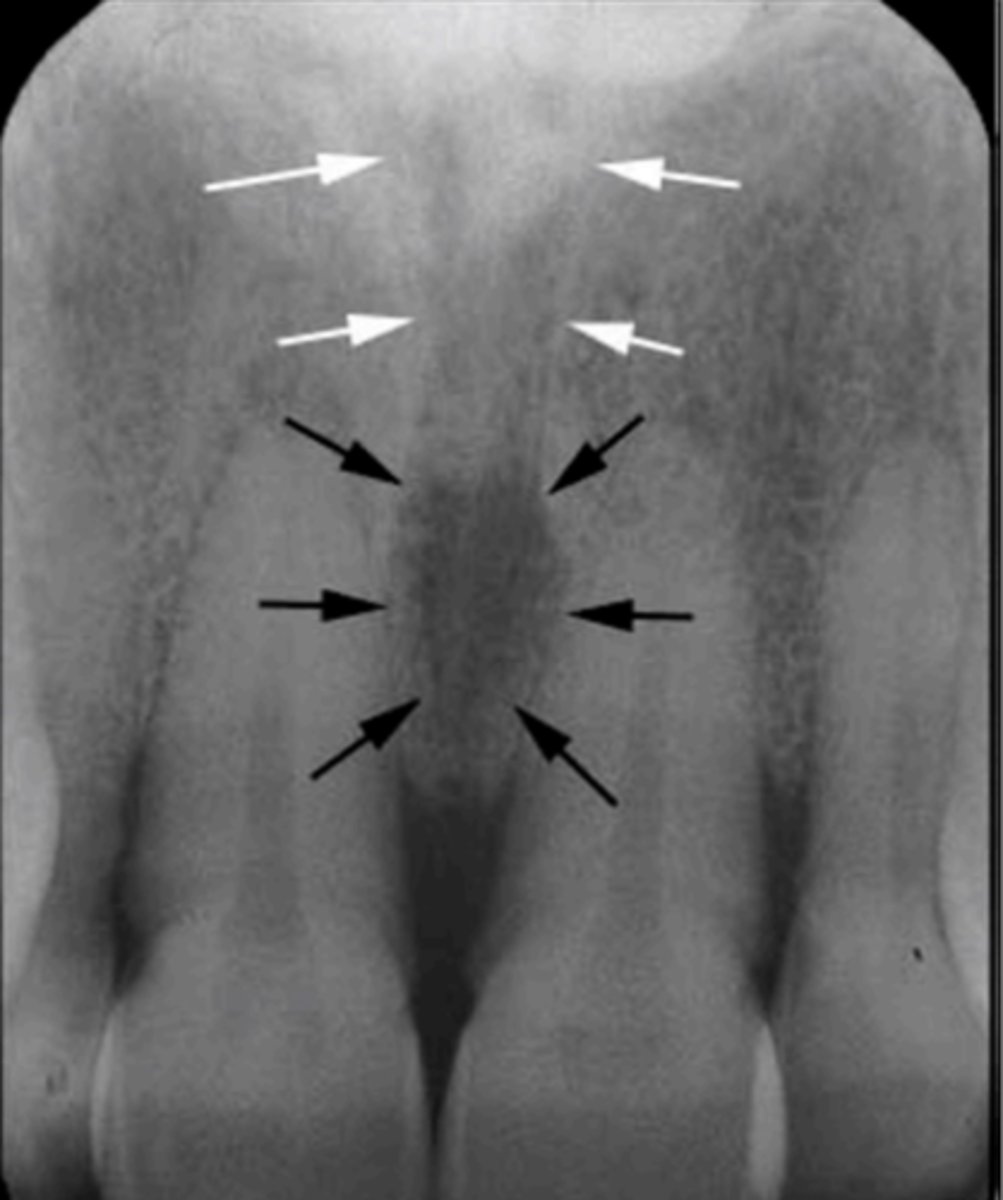

Black arrow - Nasal septum

White arrow- nasal conchae

Identify both structures

Nasopalatine (incisive) foramen

Identify the round, ovoid radiolucent structure indicated by the black arrows.

Nasopalatine canal

Identify the straight, radiopaque lines indicated by the white arrows.